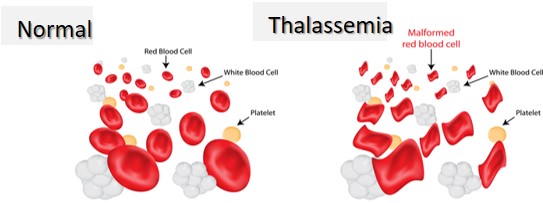

Tan máu bẩm sinh và vai trò của Thalassemia

Ở Việt Nam và khu vực châu Á, Alpha Thalassemia thể nặng là nguyên nhân di truyền có thể gây thiếu máu thai nhi rất sớm và rất nặng.

Trong thể Hb Bart’s, thai không tạo được hemoglobin hoạt động hiệu quả. Hậu quả là thiếu máu tiến triển nhanh và có thể dẫn đến phù thai toàn thân.

Cần làm rõ rằng Beta Thalassemia thường không gây thiếu máu nặng trong giai đoạn bào thai do còn hemoglobin F bảo vệ. Việc phân biệt này giúp tránh hoảng loạn không cần thiết ở những gia đình chỉ mang gen Beta Thalassemia.

Nếu nghi ngờ tan máu bẩm sinh, cần xét nghiệm di truyền cho bố mẹ và đánh giá thêm khi cần thiết.